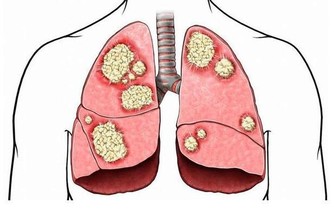

喝水喝得少,就無法排出體內的毒素,時間長了,體內毒素累積,就可能對腎臟造成損傷。腎結石的形成原因之一也是由於水喝的少導致的。

在臨床上,經常能看到患有腎結石的人,但是患者本人往往意識不到,腎結石的常見臨床表現有哪些呢?

除此之外,結石可能會損壞腎的微小血管,造成血尿,某些人還會表現為尿頻、尿急和尿痛等。